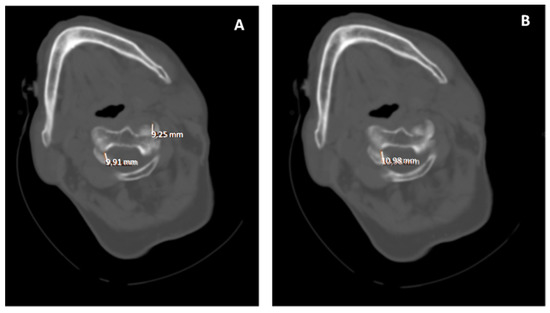

5.2. Computed Tomography (CT)